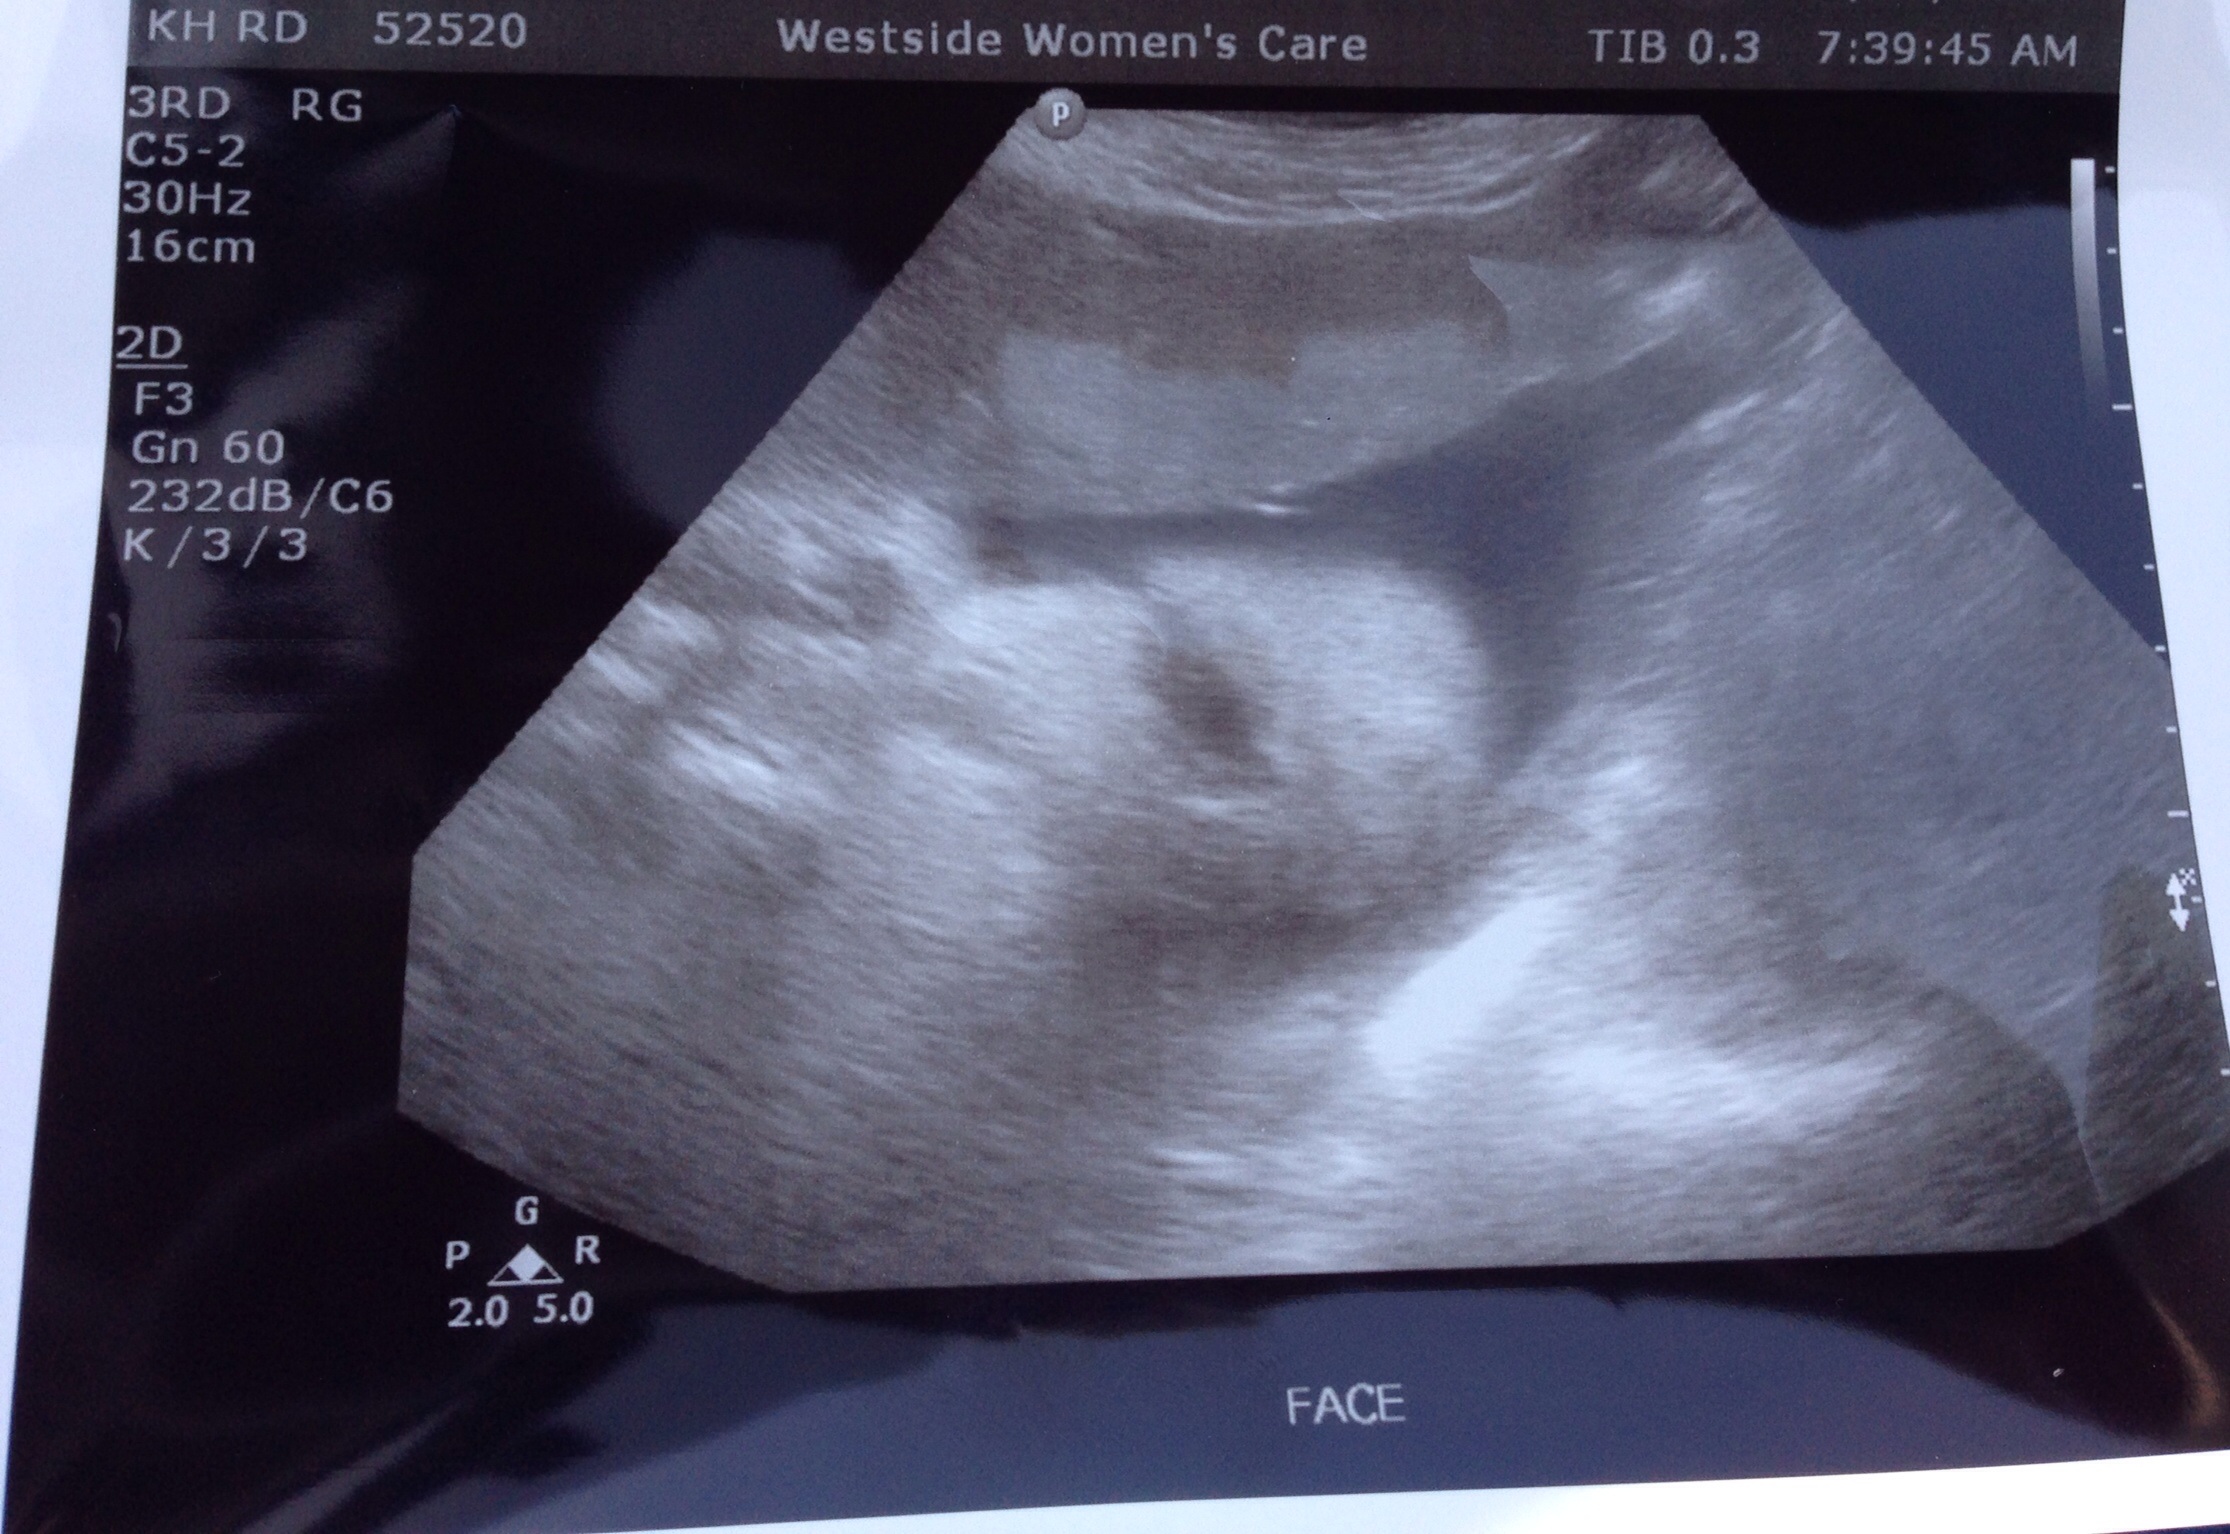

image